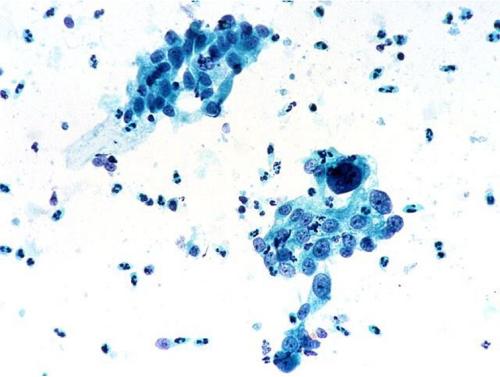

日,科學家們開發(fā)出了一種能夠檢測所有類型癌癥的新型檢測技術(shù),這種技術(shù)基于一種特殊的DNA標記,這種DNA標記在所有類型癌癥中都存在。目前這項測試還沒有在人類機體中進行,在研究人員確定其是否能用于人體之前還需要進行大量的臨床試驗。 ?????? 不管是乳腺...